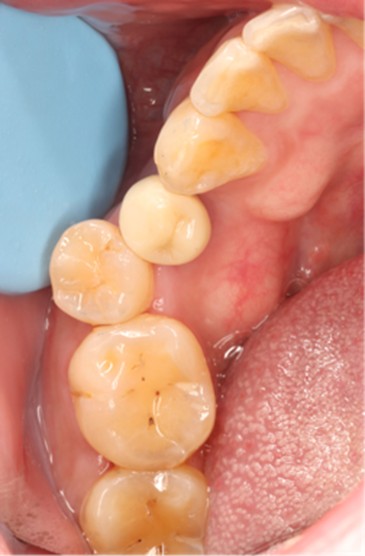

Postoperative CT scans and intraoral photographs were obtained.

November 23, 2025: Implant follow-up examination. The implant surgical site showed excellent healing, with no abnormal bone density around the implant and satisfactory osteogenesis. The third-stage impression taking was implemented. The panoramic radiograph below confirmed the complete seating of the implant impression coping.

December 4, 2025: Definitive crown delivery. The margin of the implant-supported crown exhibited optimal adaptation.